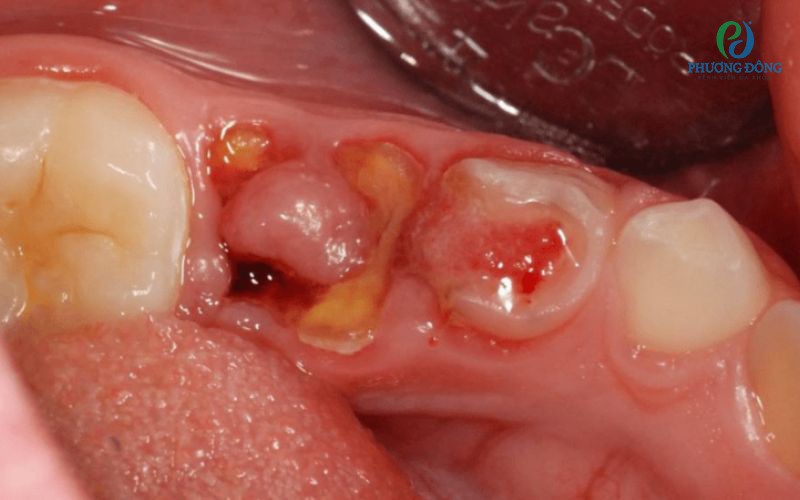

Giai đoạn khối u phá vỡ bề mặt xương

Ở giai đoạn này, các tổn thương thường xuất hiện ngay dưới lớp niêm mạc. Người bệnh có thể sờ thấy các khối u nổi lên nhưng hầu như không cảm thấy đau hay khó chịu khi chạm vào. Bề mặt xương quanh vùng tổn thương thường trở nên mỏng và sắc hơn bình thường, cho thấy cấu trúc xương đã bị ảnh hưởng.

Giai đoạn u xương tạo đường do và gây biến chứng

Khi bệnh tiến triển, niêm mạc bao phủ khối u dần trở nên mỏng, dễ bị thủng, tạo thành các lỗ dò thông ra khoang miệng hoặc bên ngoài da. Lúc này, người bệnh có thể xuất hiện hiện tượng chảy dịch hoặc đau nhẹ tại vị trí tổn thương.